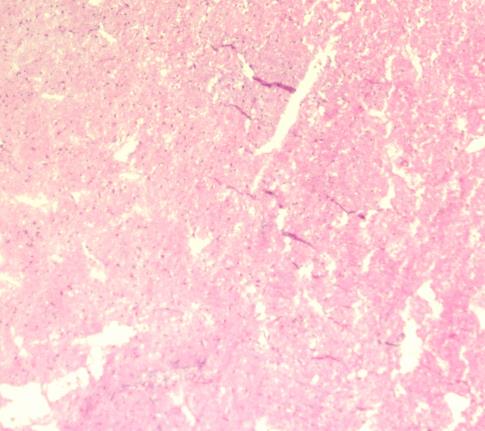

房室结镜下情况

肺脏镜下情况